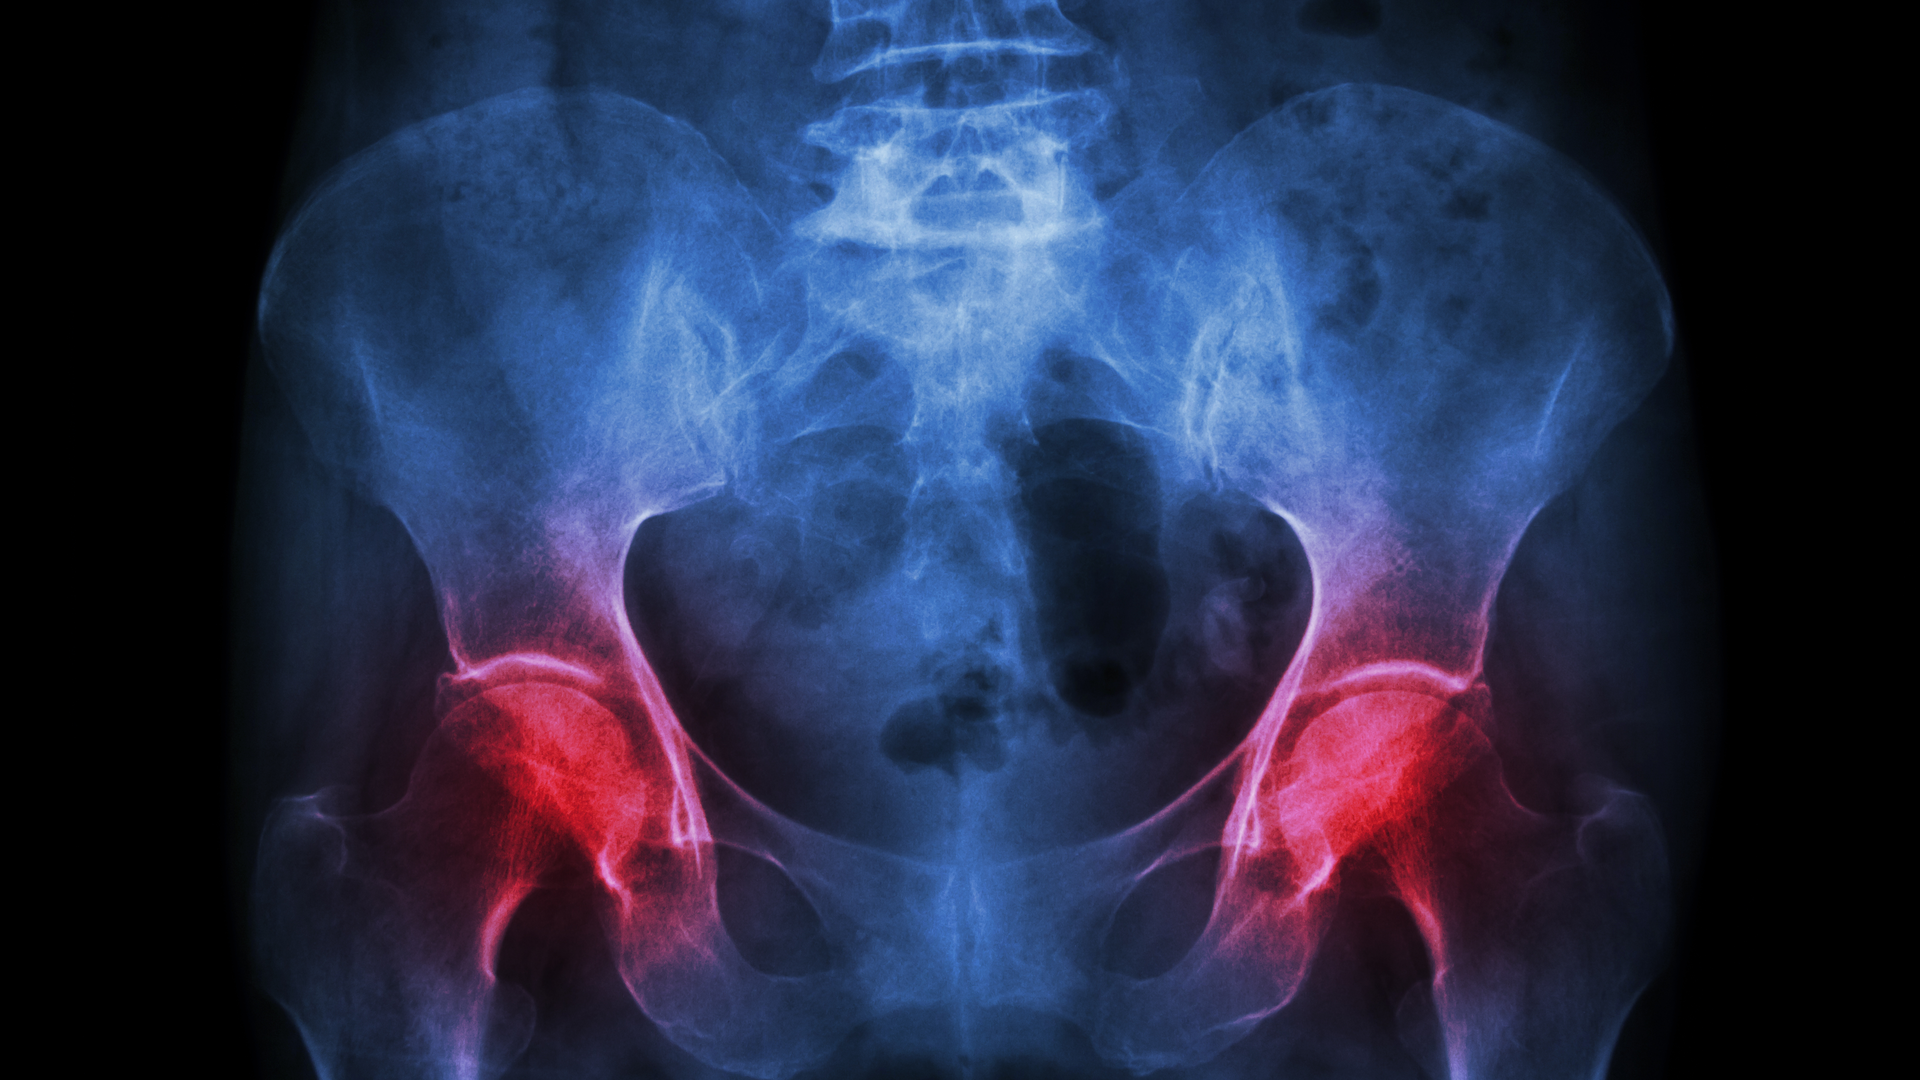

Fibrous dysplasia stems from gene mutations that cause scar-like (fibrous) tissue to replace healthy bone starting in early childhood. These fibrous lesions, which are marked by accelerated bone turnover, weaken bones, leading to bone deformities, fractures, physical disabilities, and pain. In some cases, the lesions can press up against organs and nerves, impairing functions like vision and breathing.

In the phase 2 clinical trial, eight women received high doses of denosumab over six months. At the end of the treatment period, patients’ bone biopsies and scans showed a marked reduction in bone turnover within lesions. Proteins in the blood associated with bone turnover also dropped to normal levels. These results indicated that the treatment improved the quality and strength of patients’ bones.